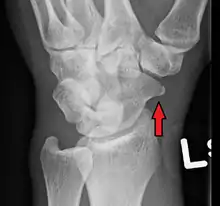

A subtle scaphoid fracture

A more obvious scaphoid fracture on a scaphoid view X ray

Radiolucency around a 12 days old scaphoid fracture that was initially barely visible.[12]